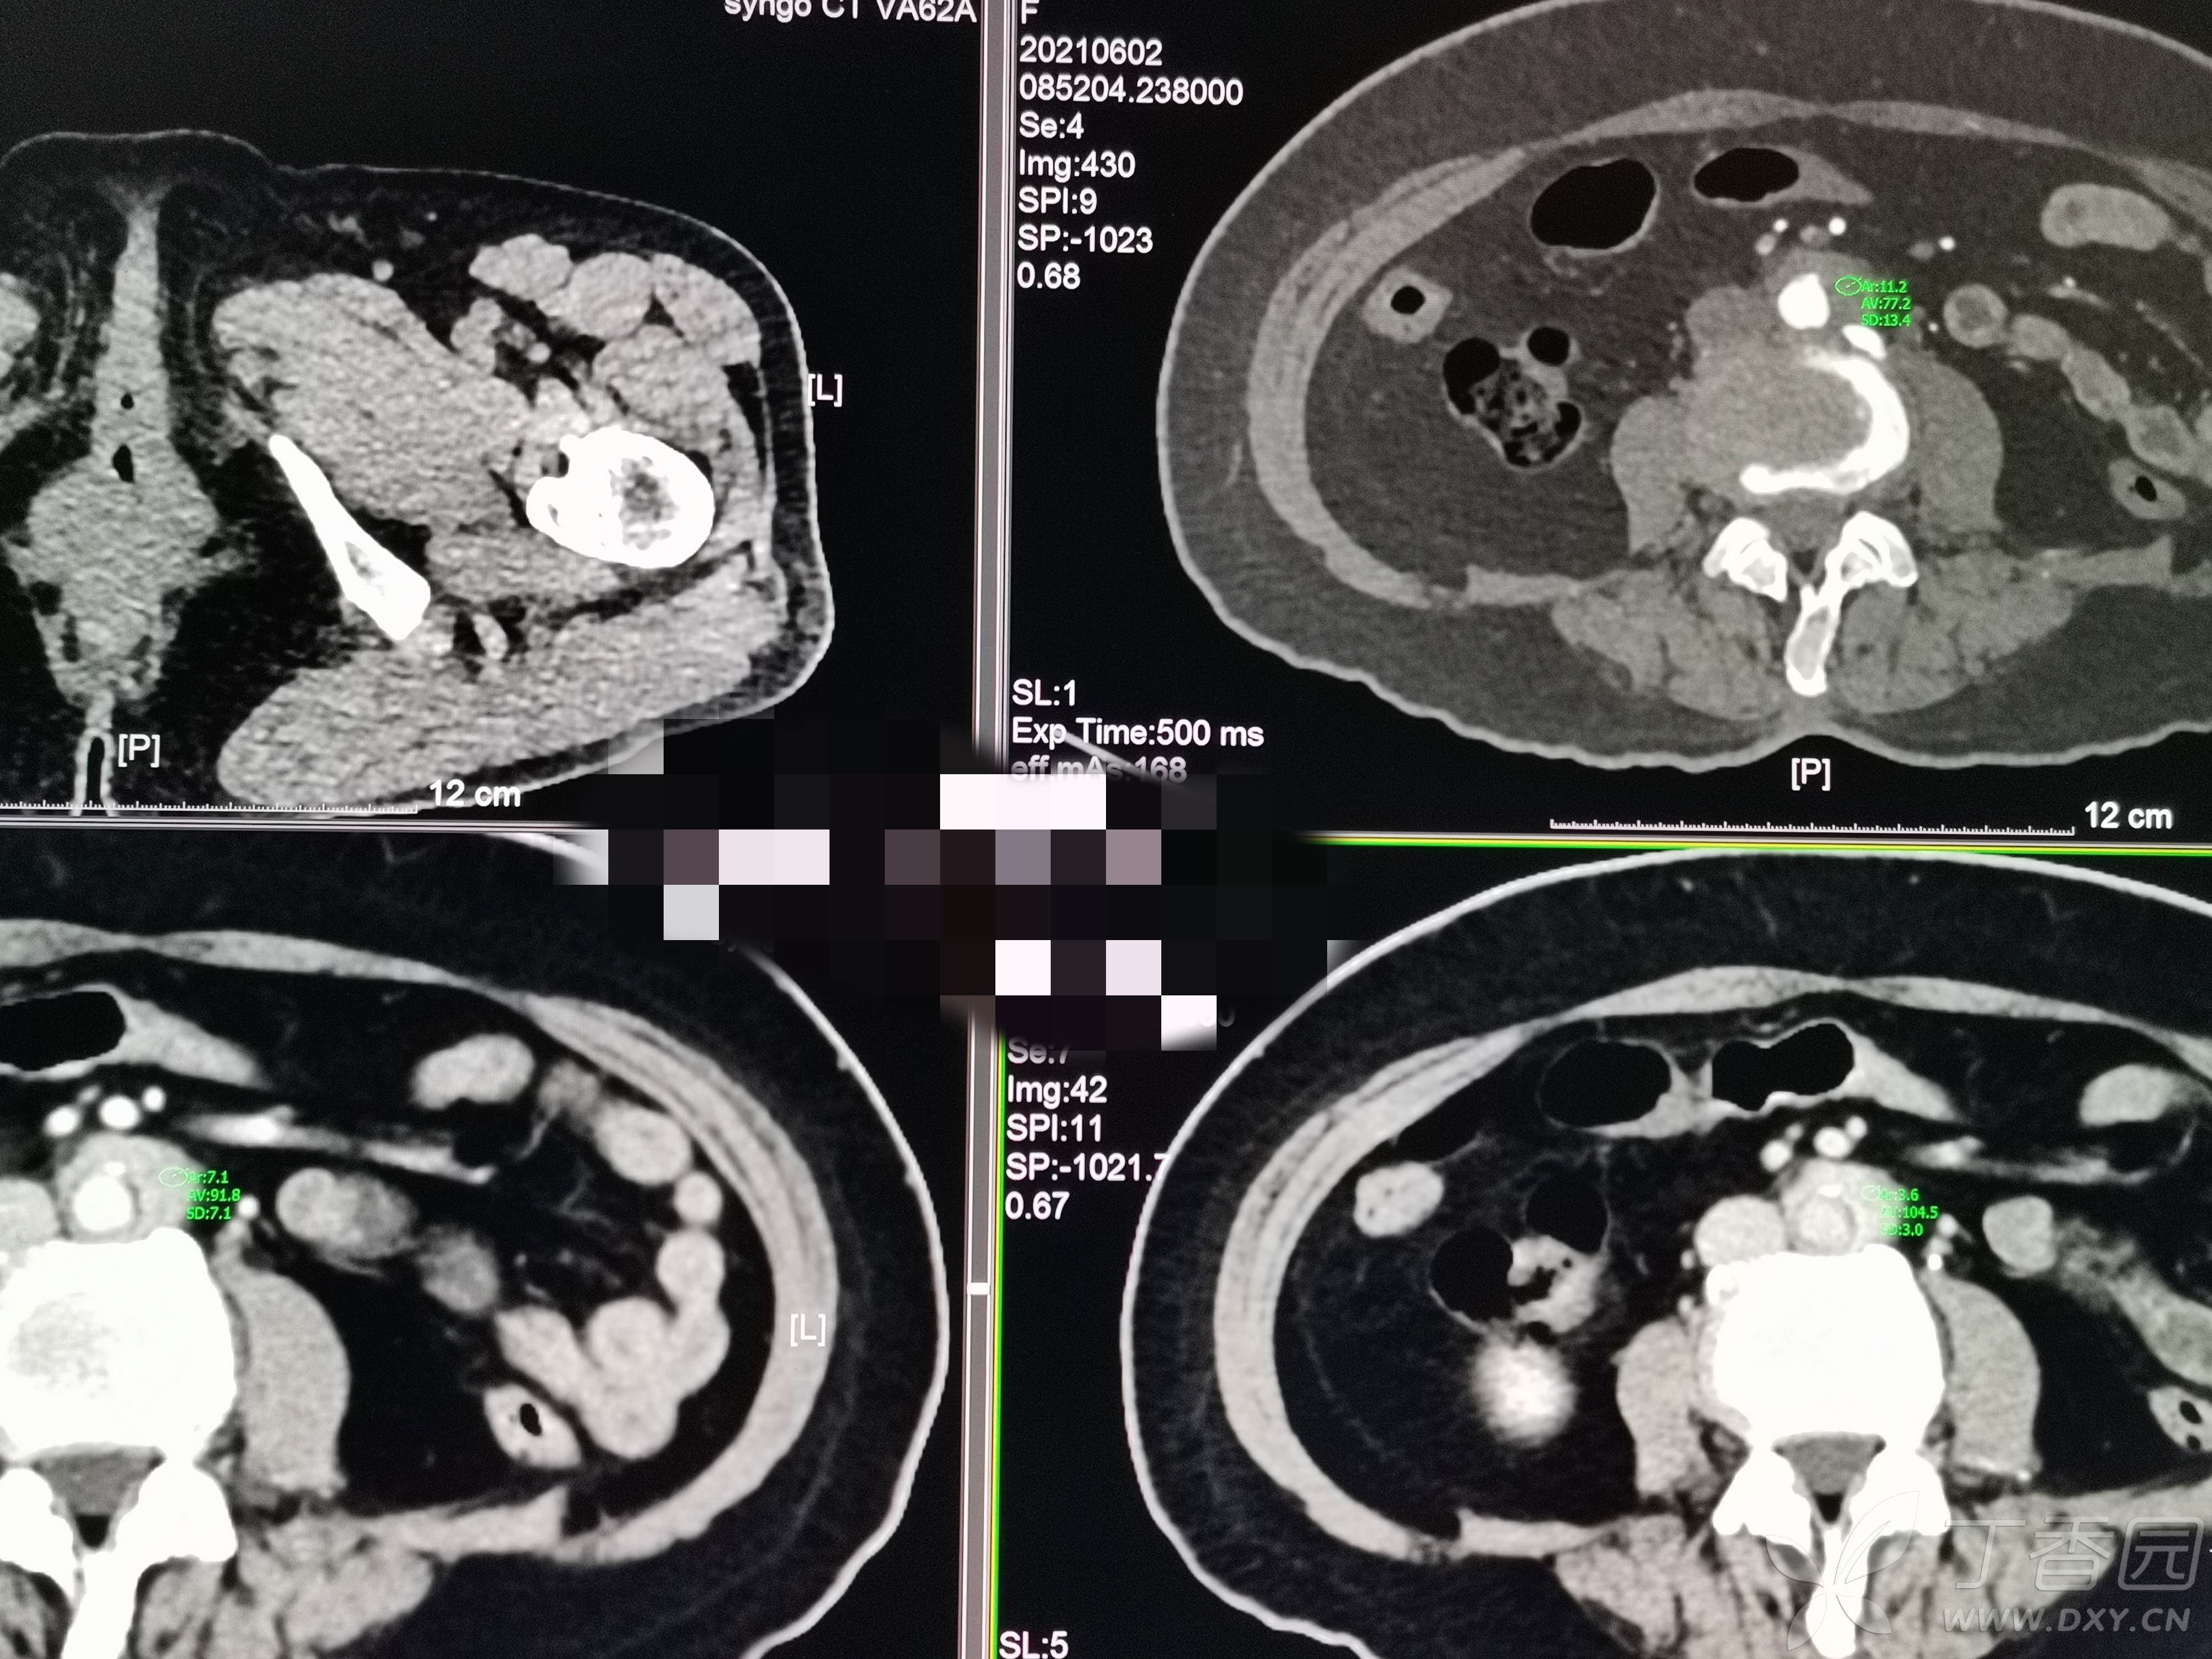

求助 | 女,61岁,下腹部、腰及双髋关节隐痛1月余

II型糖尿病10年余,既往饮食控制血糖在7~8左右,今年1月份开始服用二甲双胍;2009年4月因“子宫肌瘤、双侧输卵管慢性炎症”行子宫及附件切除术;2021年1月体检发现双侧甲状腺多发结节,较大者12*7mm;高血脂10余年,近1月开始规律服药,控制不理想;无高血压